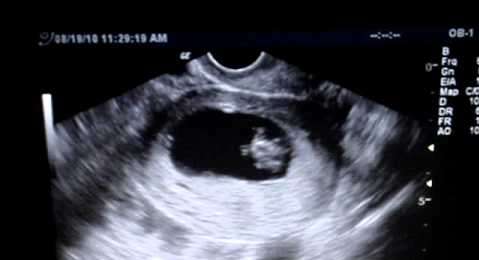

كيف اعرف نبض الجنين في الشهر الثاني؟ اكتشفي الجواب على هذا السؤال مع عائلتي التي تعرفك على نبض الجنين في الشهر الثاني وعلى علامات واسباب توقفه.

تتساءل المرأة الحامل عن حركة الجنين في اشهر حملها الأولى لتتأكد ان جنينها بخير ومن أن حملها ثابت في هذه الشهور، ولكن من البعيد جداً الشعور بحركة او نبض الجنين في اول ثلاث شهور من الحمل، وللإطمئنان على صحة الجنين في الشهر الثاني من الحمل، ينبغي اجراء فحص التصوير بالموجات فوق الصوتية في عيادة الطبيب المختص. ومن أبرز الأعراض لمعرفة ان الجنين بخير وموجود هي اعراض الغثيان والقيئ لأنها تُعتبر من اهم علامات الحمل الأولى.